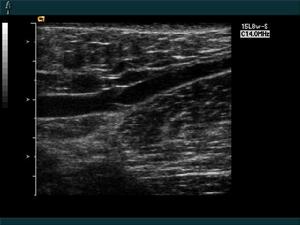

血管超聲檢查(2)甲皺微循環檢查示毛細血管袢輪廓模糊、擴張,其內壓力增高,給予熱刺激後更為嚴重。

(4)血管超聲檢查。